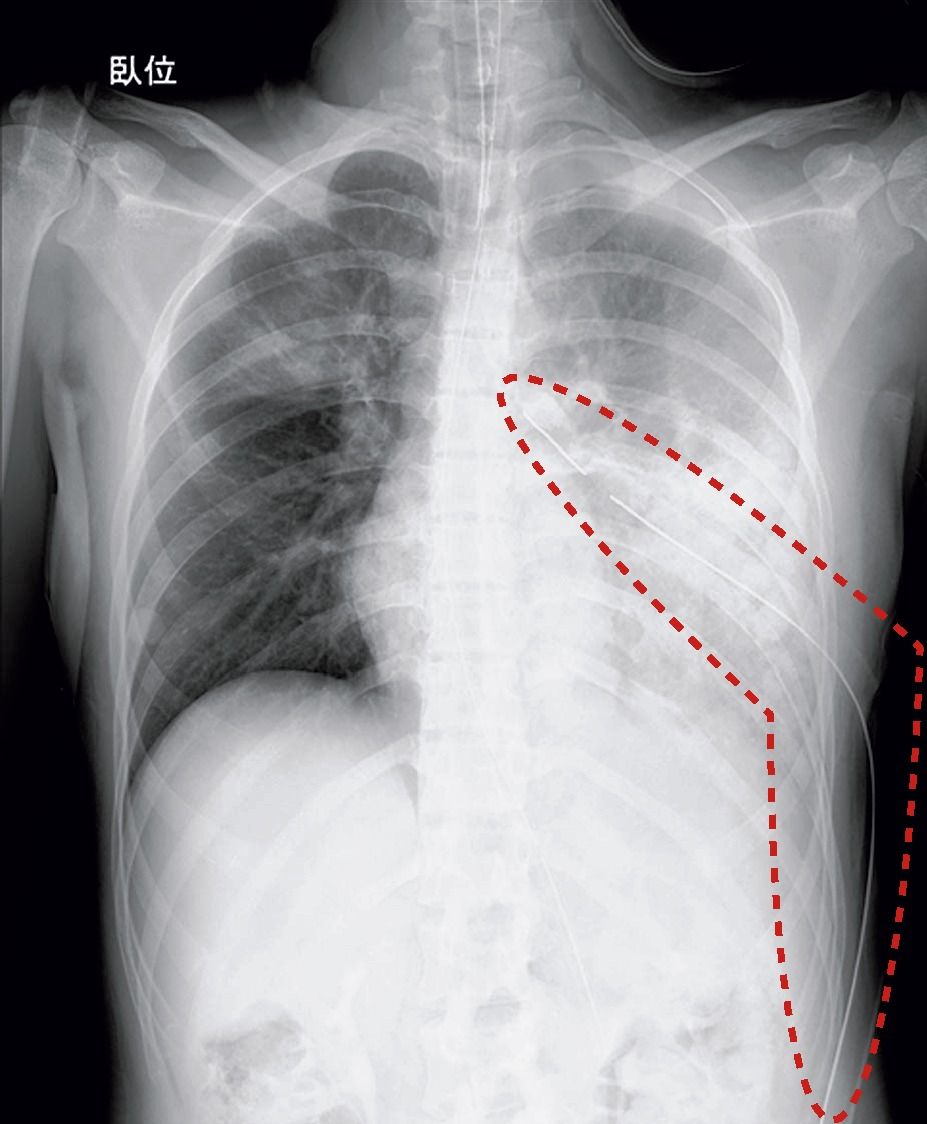

連載「交通安全・医理工連携の今 『世界一』への挑戦」(103)佐々木勝教 交通事故と外傷(6)胸部外傷(肋骨骨折)

胸部には生命維持に非常に重要な臓器(肺、心臓、大血管など)が存在します。交通事故での胸部の外傷は、死に直結する場合も多く、迅速で的確な対応が必要です。 これらの重要な胸部の臓器は、強固な骨性の胸壁に囲まれ守られています。骨性胸壁のなかでも...